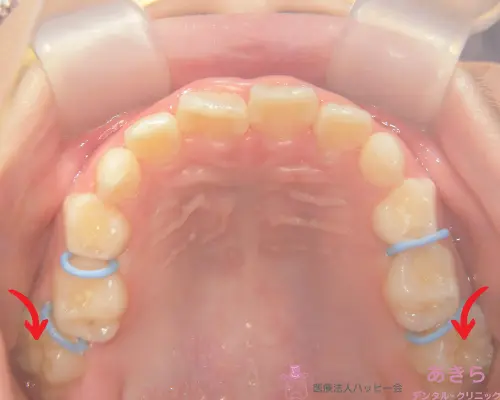

※青印 ⇒ 上記改善もしくは改善傾向

経過時(リンガルアーチスタート)

上顎左右6歳臼歯が外に生えて下の6歳臼歯と噛まない状態

経過時(リンガルクリート装着~ゴム牽引開始)

特に噛み合わない右上下6番に赤矢印はリンガルクリート装着=ゴムを掛けて位置補正を繰り返す

赤印=左右6歳臼歯が噛んできました